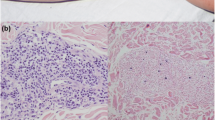

Prior to the identification of EBV-naïve patients, it was thought that the observed lymphadenopathy (LAD) in XMEN was primarily due to EBV infection. However, we recently reported that LAD was also frequently seen in EBV-naïve patients, while splenomegaly was mostly observed in about 50% of the EBV-infected patients [4]. In our NIH cohort, most patients have mild LAD involving the cervical, axillary, intra-abdominal, and/or inguinofemoral lymph nodes bilaterally. Histopathological examination of lymph node (LN) biopsies from two EBV-naïve children were consistent with Castleman disease, with an atypical B cell population co-expressing the CD5 marker identified in one of these cases [4, 12]. Reactive lymphoid hyperplasia has been observed in LN biopsies from both EBV-naïve and EBV-infected patients [4]. Follicular hyperplasia with or without atypical lymphoid proliferation and increased number of EBV-positive cells have been reported in LN, tonsillar and adenoidal tissue biopsies from EBV-infected individuals [4]. Histopathology of the terminal ileum of an EBV-infected patient showed reactive mucosal lymphoid follicles [4]. An atypical perivascular EBV+ lymphoproliferative cutaneous lesion was also recently reported in a young adult with a history of multiple EBV-associated lymphomas [12].

Asymptomatic transient elevations in aspartate aminotransferase (AST) and alanine aminotransferase (ALT) are common in XMEN and were observed in all of our patients [4]. Although some patients have sustained transaminase elevations, most patients have fluctuations in their liver enzymes, including determinations within the normal range. This is true for both EBV-naïve and EBV-infected patients. None of the patients in our NIH cohort had impaired hepatic function, gamma-glutamyl transpeptidase (GGT) levels were mostly normal, and hepatitis serologies were all negative [4]. Although autoimmune hepatitis (AH) has been reported for one case, we did not find any serologic or histopathological evidence of AH in a larger cohort of patients [4, 44]. Varying degrees of inflammation, fibrosis, hepatosteatosis, iron deposition, and diffuse glycogenosis were seen in both EBV-infected and EBV-naïve patients [4]. Hepatic biopsies from patients with EBV viremia did not show a pattern of injury consistent with EBV-associated hepatitis and were Epstein-Barr encoding region (EBER) negative [4]. Taken together, these findings suggest that the liver abnormalities in XMEN are not related to EBV-infection and may be secondary to the underlying NLG defect [4].